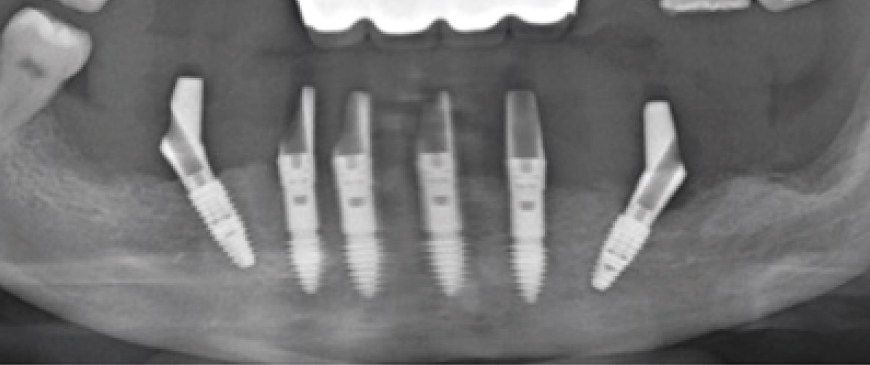

The plan involves placing 6 to 8 implants, evenly distributed across the available space.

Fig 4

It is always better to choose ‘Palatal positioning’ in the Upper Thin Ridge for long-term stability. In this case, 4 ARi (3.2) 4.5x7.0(6) implants and 2 BlueDiamond implants were placed, totaling 6 implants in ideal positions. The Knife Thread of the ARi implant smoothly integrated into the thin ridge without causing any damage, ensuring optimal stability and positioning.

Post-surgery panoramic and CBCT radiographs show that all implants in the posterior and anterior regions were placed in stable positions. Since the fixture threads of all implants were securely integrated into the bone, a secondary surgery was scheduled approximately 10 weeks later.